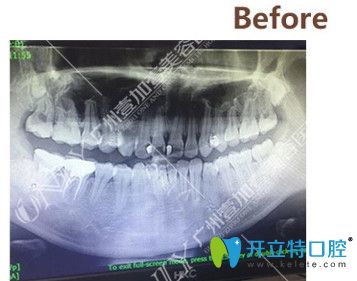

▼矯正前拍攝的CT

矯正前拍攝的CT

拍了CT之后,醫(yī)生根據(jù)我的情況給我進(jìn)行了分析,我的情況還不算特別復(fù)雜,牙套可以選擇金屬的、半隱形的以及隱形的,問清楚了這幾種牙套的區(qū)別和價(jià)格之后,我選擇了價(jià)格中等,美觀度稍高的半隱形陶瓷牙套。